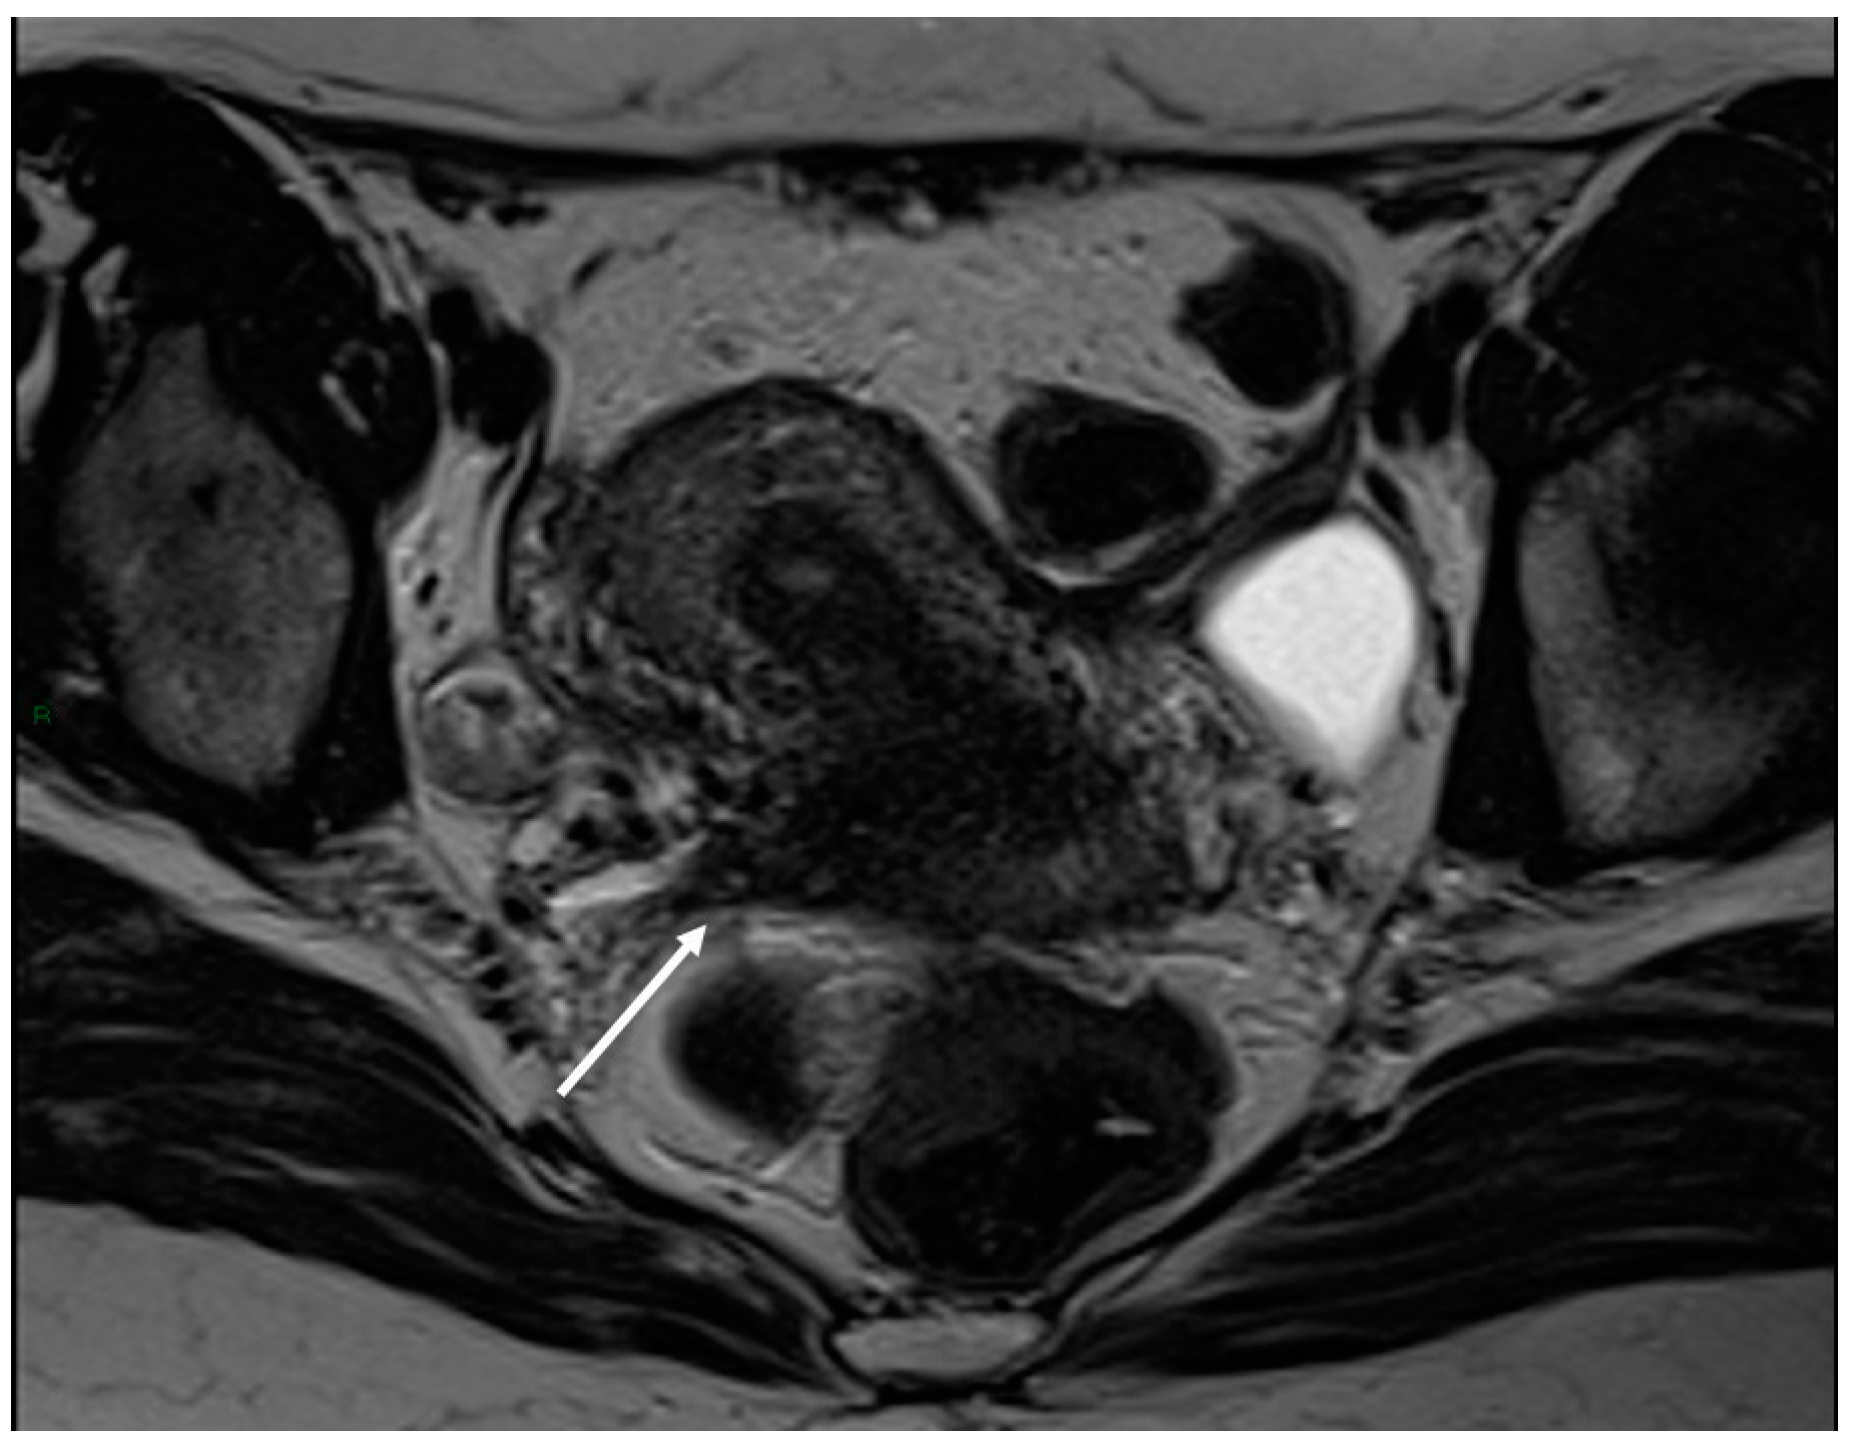

3.2.5. Rectosigmoid Colon

- Rousset, P.; Florin, M.; Bharwani, N.; Touboul, C.; Monroc, M.; Golfier, F.; Nougaret, S.; Thomassin-Naggara, I.; ENDOVALIRM Group. Deep Pelvic Infiltrating Endometriosis: MRI Consensus Lexicon and Compartment-Based Approach from the ENDOVALIRM Group. Diagn. Interv. Imaging 2023, 104, 95–112. [Google Scholar] [CrossRef]

- Bazot, M.; Kermarrec, E.; Bendifallah, S.; Daraï, E. MRI of Intestinal Endometriosis. Best Pract. Res. Clin. Obstet. Gynaecol. 2021, 71, 51–63. [Google Scholar] [CrossRef] [PubMed]

- Tang, X.; Ling, R.; Gong, J.; Mei, D.; Luo, Y.; Li, M.; Xu, J.; Ma, L. Deep Infiltrating Endometriosis MR Imaging with Surgical Correlation. Quant. Imaging Med. Surg. 2018, 8, 187–195. [Google Scholar] [CrossRef] [PubMed]